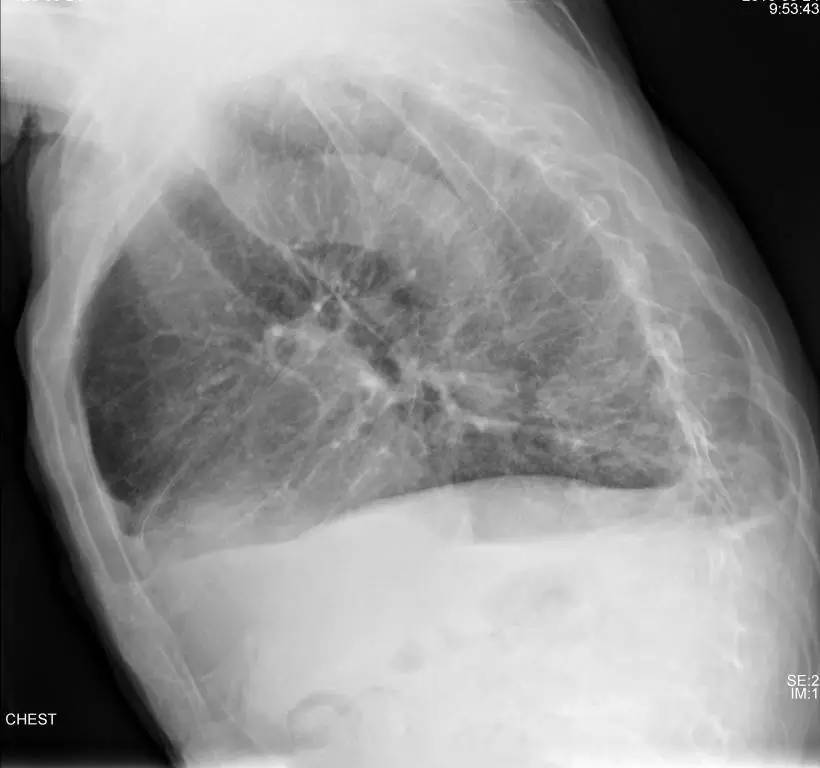

>>>>病例3:女,89岁,慢阻肺多年。

左侧胸腔最有可能的诊断是?

A.包裹性积液

B.胸膜增厚

C.胸腔积液

D.心包脂肪垫